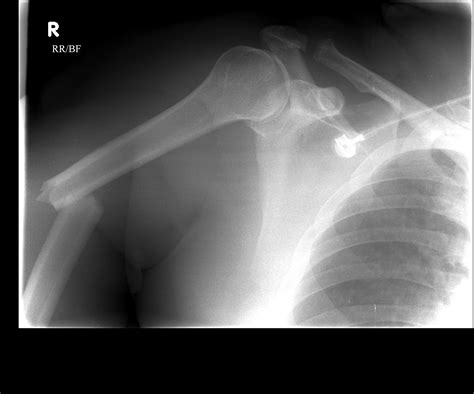

Diagnosis of Humerus Bone Head Fracture

Diagnosing a humerus bone head fracture involves a combination of physical examination and imaging tests. The diagnostic process typically includes:

• Physical Examination: The doctor will assess the shoulder for pain, swelling, and deformity.

• X-Rays: Standard imaging to visualize the fracture and determine its severity.

• CT Scan: For more detailed images, especially if the fracture is complex or involves the joint.

• MRI: To evaluate soft tissue damage and assess the extent of the injury.